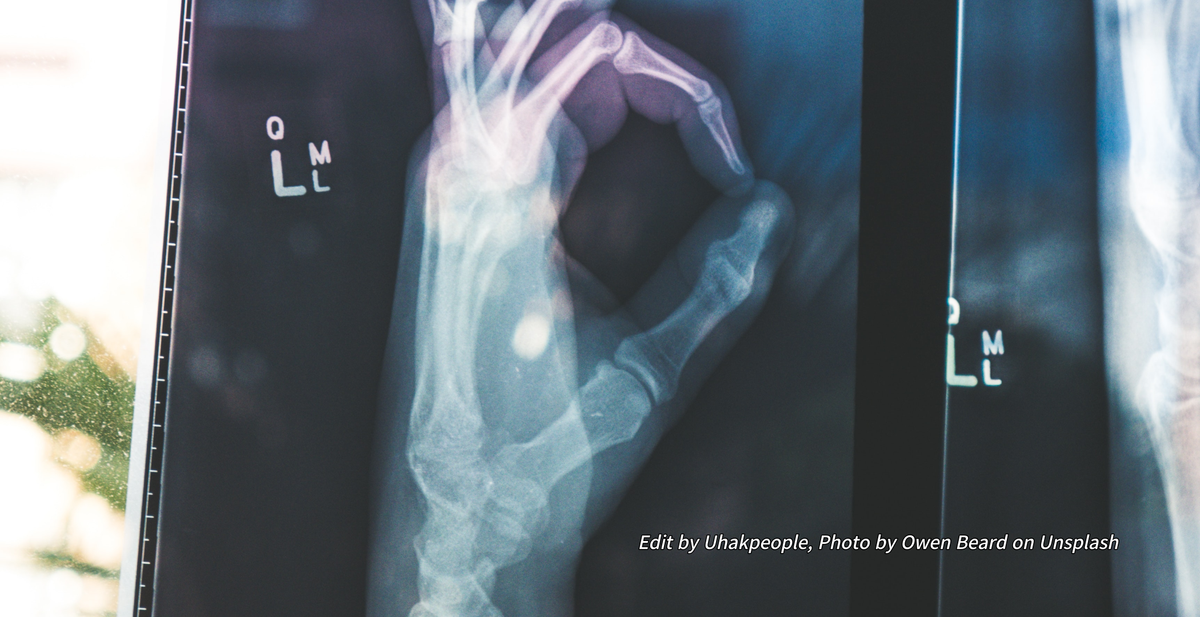

두 번째로 소개해 드릴 보건계열은 방사선학과입니다. 이름에서도 알 수 있듯이 방사선사를 양성하기 위한 학과입니다. 팬쇼에서도 상당히 인기가 높은 전공이며 이민을 준비하는 분들이 가장 많이 선택하는 전공 중 하나입니다. 그 이유는 아무래도 취업률과 연봉에 있을텐데요. 취업률이 상당히 높으며 연봉도 평균 5만 달러에 달합니다.

우리나라의 방사선와 하는 일은 비슷한데요. 엑스레이나 CT 등 영상의학을 다루는 전문직종으로 대형병원이나 일반 병원으로 취업을 하게 되며 병원 내에서 다소 차별을 받는 우리나라의 방사선사와는 달리 캐나다의 방사선사는 의사에 준하는 대우를 받으면서 일을 하고 있습니다. 앞서 설명을 드렸듯이 보건계열 학과들은 수업의 난도가 높기 때문에 입학 조건도 까다롭고 Pre-Health 과정도 필수적으로 들어야 합니다. 예외적으로 물리치료보조사는 Pre-Health 과정을 듣지 않아도 됐지만 방사선학은 필수로 들어야 합니다.